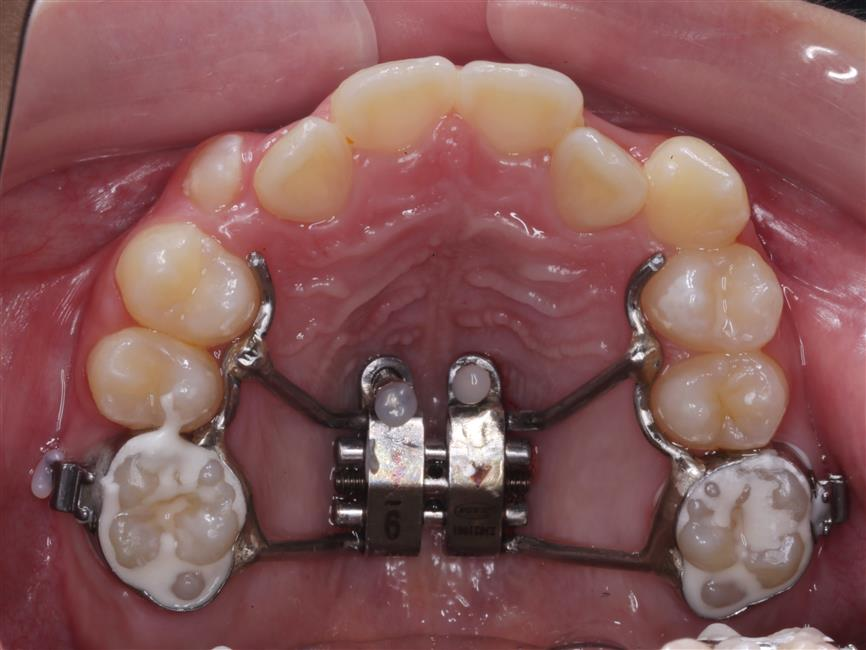

Để giải quyết triệt để các vấn đề trên, đội ngũ bác sĩ đã xây dựng một phác đồ điều trị cá nhân hóa và chi tiết cho Hương Giang. Trọng tâm của quá trình là phương pháp kéo lui hàm trên có kiểm soát.

Điểm sáng trong phác đồ điều trị của Giang là việc ứng dụng Minivis (vít niềng răng) trong chỉnh nha. Việc cắm Minivis tạo ra một điểm neo chặn vững chắc tuyệt đối trên xương hàm, giúp bác sĩ kiểm soát lực kéo tối ưu. Nhờ đó, các răng được chỉ định dịch chuyển một cách chính xác về đúng vị trí mong muốn trên cung hàm, đảm bảo hiệu quả cao và tính ổn định lâu dài.